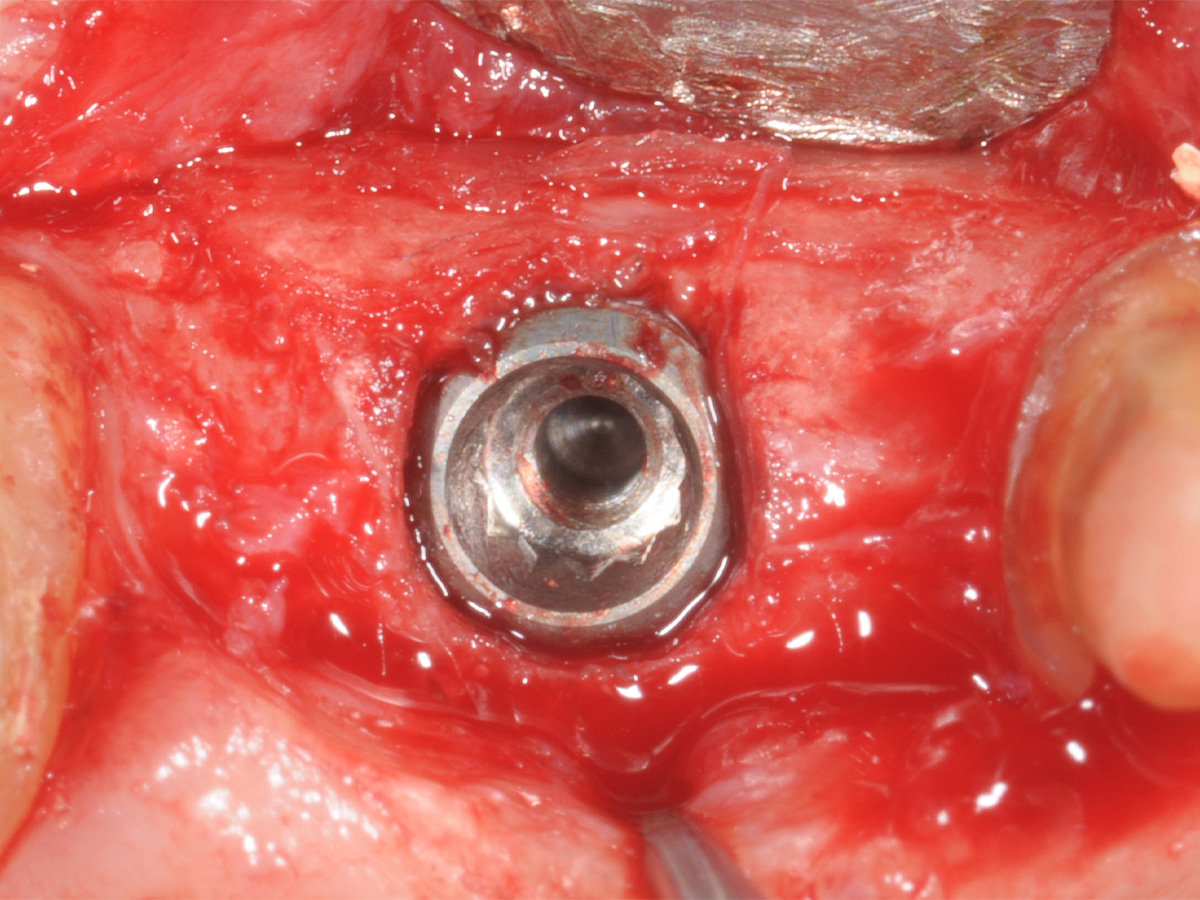

Abbildung 14

Freilegung mittels modifiziertem Rolllappen.